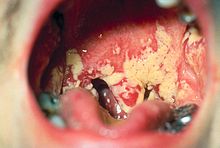

Fungal

Pseudomembranous candidiasis of the posterior mouth and oropharynx

• Oral candidiasis is by far the most common fungal infection that occurs in the mouth. It usually occurs in immunocompromised individuals. Individuals who have undergone a transplant, HIV, cancer or use corticosteroids commonly develop candida of the mouth and oral cavity. Other risk factors are dentures and tongue piercing. The typical signs are a white patch that may be associated with burning, soreness, irritation or a white cheesy like appearance. Once the diagnosis is made, candida can be treated with a variety of anti fungal drugs.[22]